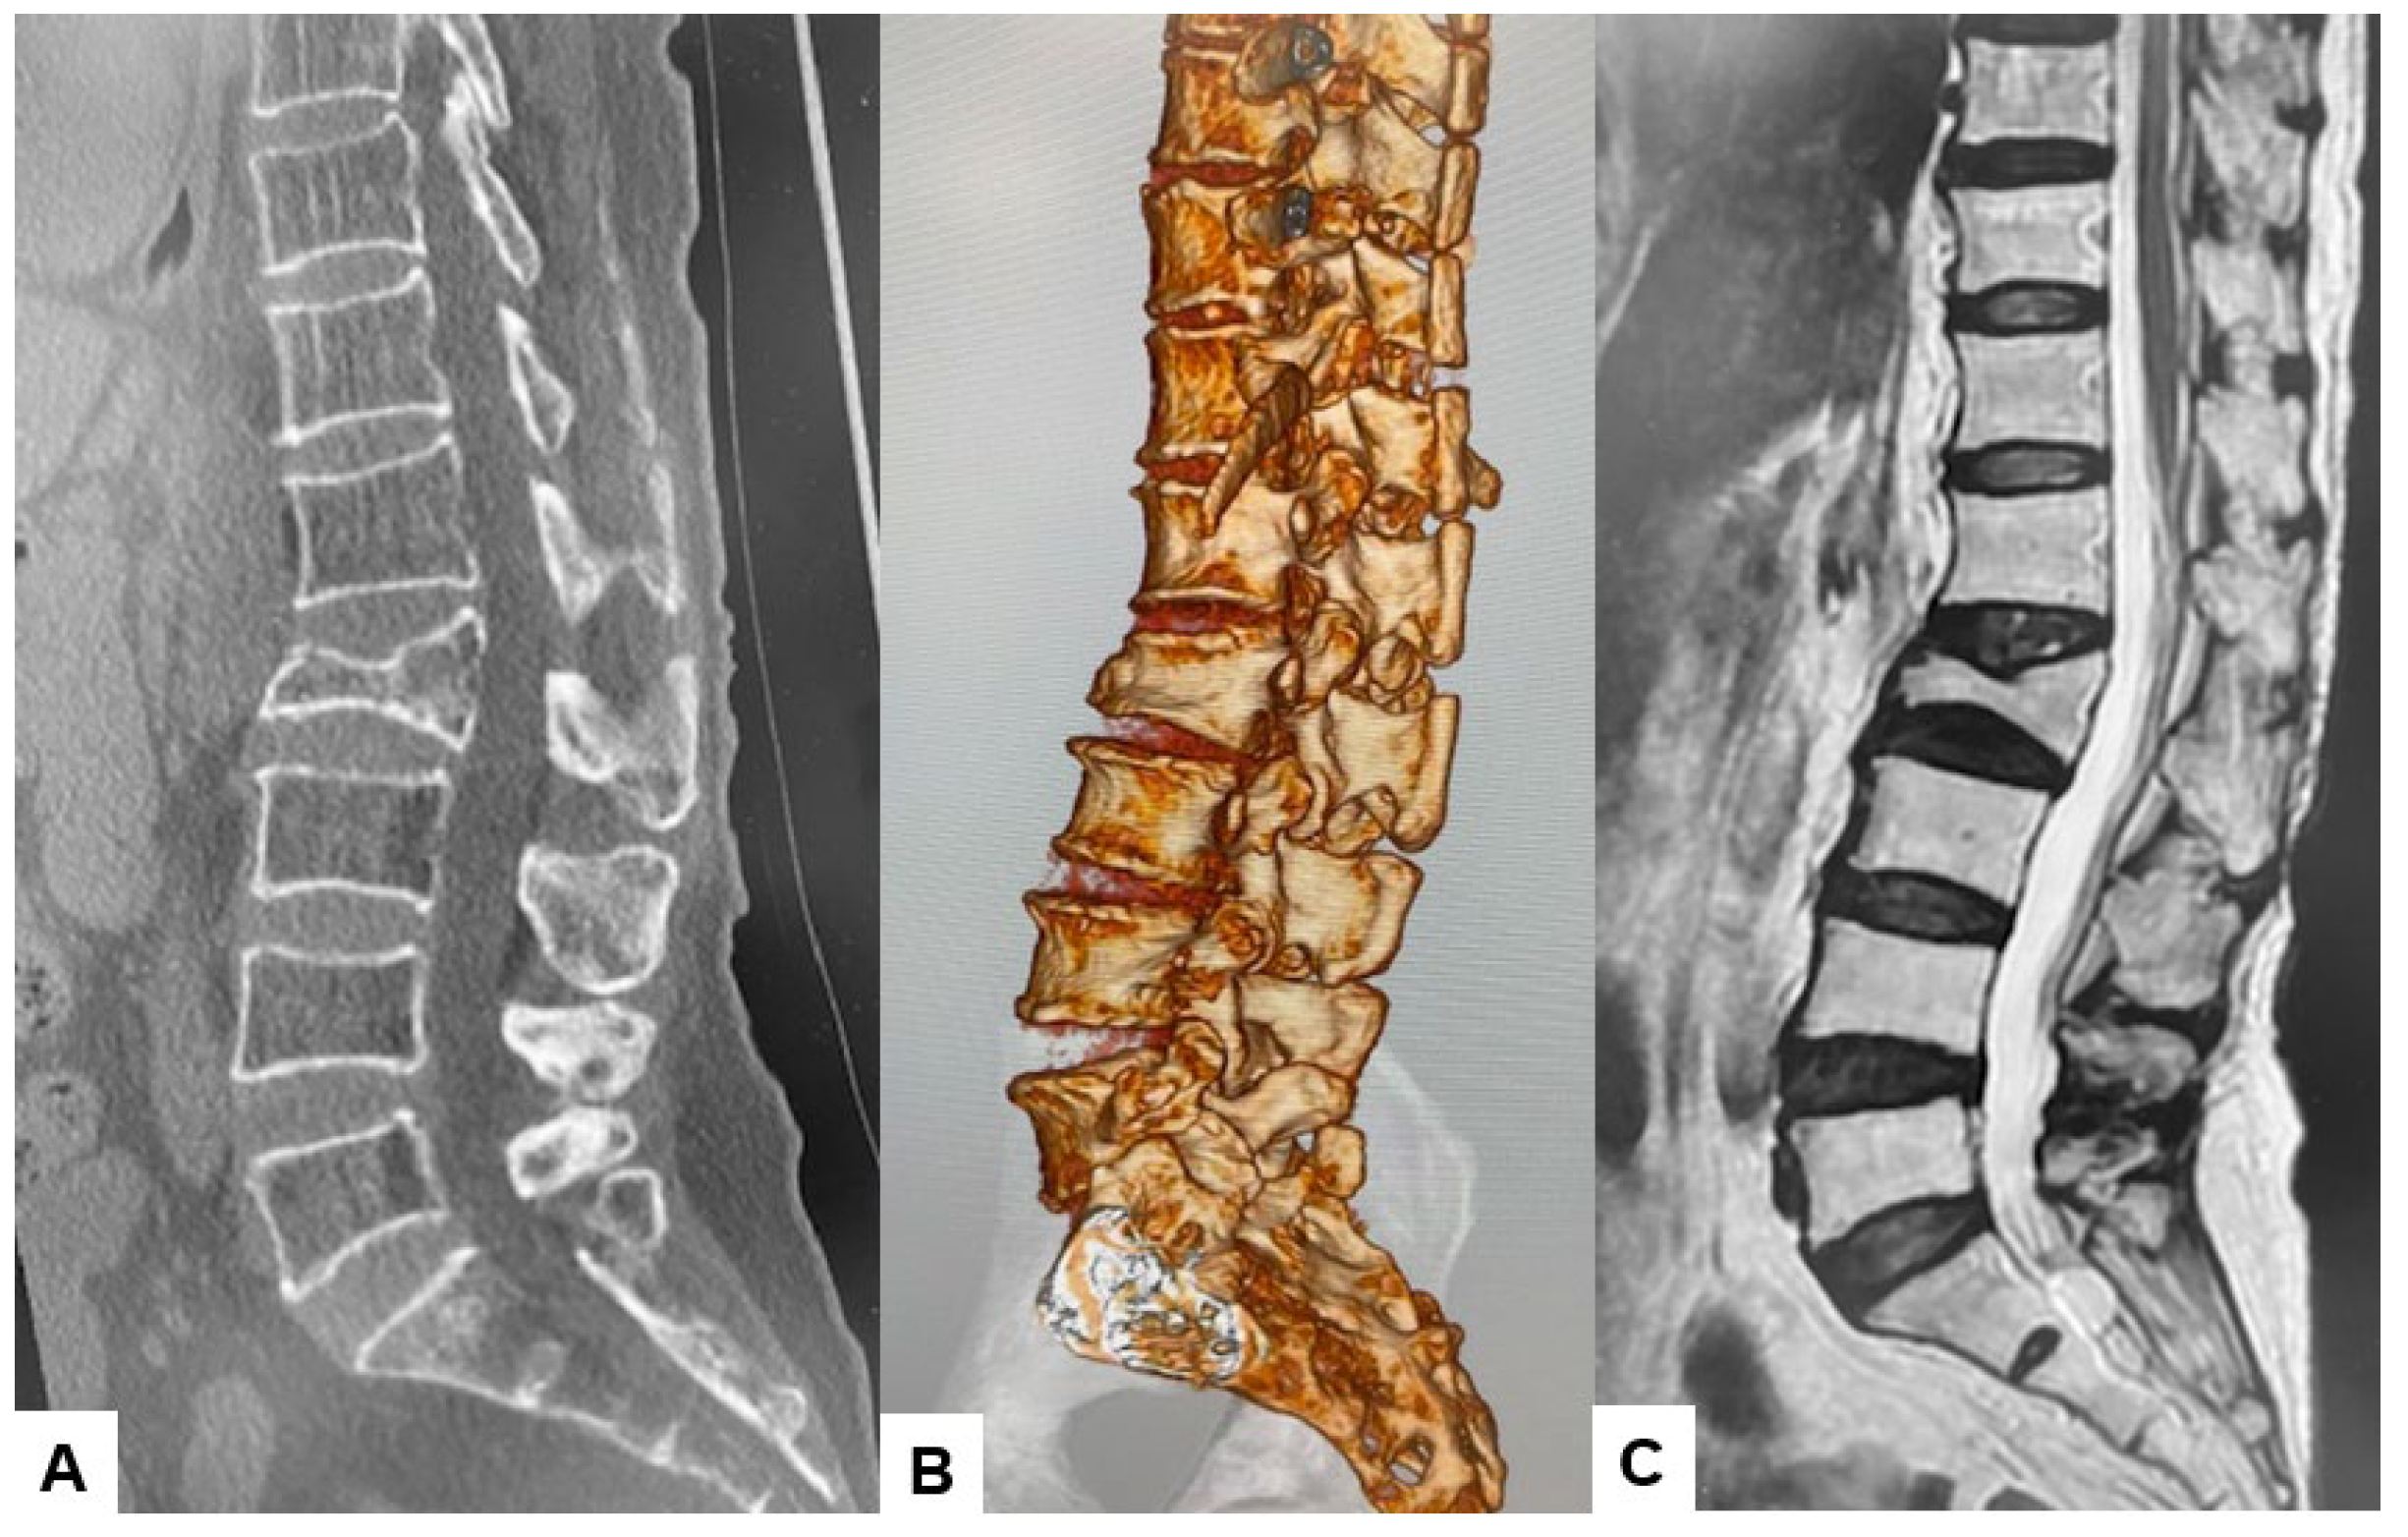

2.3. Preoperative Imaging